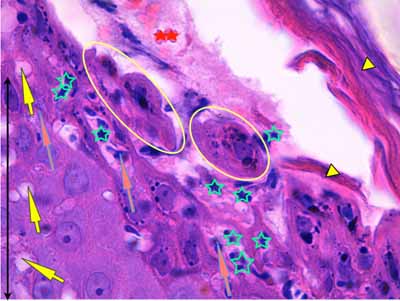

Photo 13 (Hémalun-Eosine X1000 objectif à immersion) : Vue au fort

grossissement du plancher d’une pustule intra-épidermique sous-cornée :

forte exocytose de granulocytes éosinohiles; des cellules épithéliales de la couche

granuleuse au noyau bien visible, non pycnotique, s’arrondissent et se libèrent

de leurs attaches desmosomiales, rappelant une acantholyse intra-épidermique.

Légendes de la Photo 13 :

- Pointes de flèche jaune : toit de la pustule formée de kératine orthokératosique

- Flèche oranges : exocytose transépidermique de granulocytes éosinophiles

- Flèche jaunes : spongiose épidermique ou œdème intercellulaire

- Étoiles turquoises : granulocytes éosinophiles

- Cercles jaunes : cellules épithéliales se détachant individuellement ou en petits groupes du plancher épidermique (couche granuleuse), leurs contours cytoplasmiques sont lisses arrondis et leur noyau non pycnotique, suggérant une acantholyse intra-épidermique

- Étoiles rouges : érythrocytes

- Double flèche noire : épiderme